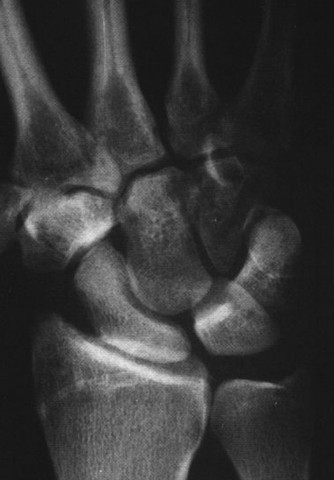

Imaging the Pisiform

Standard posteroanterior (PA) and lateral radiographs of the wrist often fail to adequately visualize the pisotriquetral joint due to bony overlap from the distal pole of the scaphoid, the capitate, and the triquetrum itself. To properly assess this articulation, a 30-degree supinated AP view (the pisotriquetral view) is mandatory. In our first patient (referencing the classic Figure 3-10), this specific view reveals profound joint space narrowing, subchondral sclerosis, and prominent osteophyte formation at the pisotriquetral interface.

It is crucial to understand the osteology here. The pisiform is an atavistic, sesamoid bone. It is the only carpal bone that does not participate in the complex intercarpal kinematics of the proximal or distal rows. Instead, it lies entirely within the tendon of the flexor carpi ulnaris (FCU). The FCU-pisiform complex extends distally via robust ligamentous attachments: the pisotriquetral ligament, the pisohamate ligament, and the piso-5th metacarpal ligament. Notably, there is no piso-scaphoid ligament; the scaphoid resides on the entirely opposite side of the carpus.